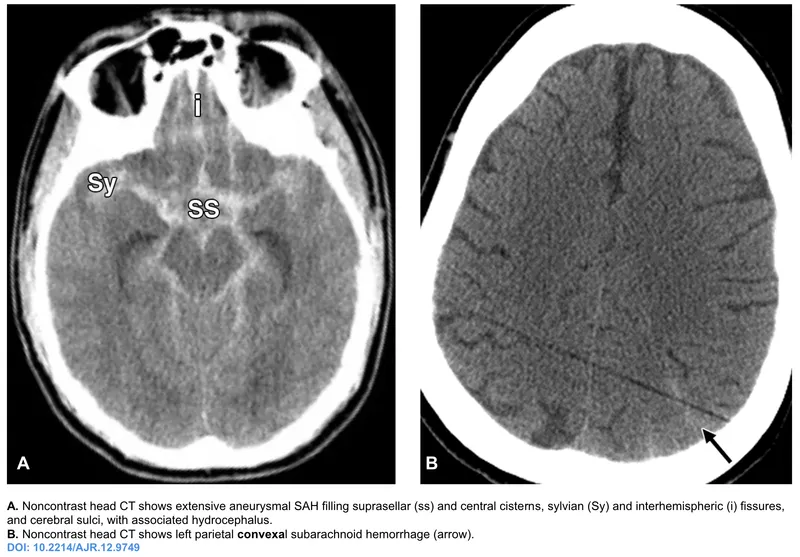

- 1st: Non-contrast head CT to detect subarachnoid blood.

⭐ Xanthochromia (yellow CSF from bilirubin) on LP is diagnostic for SAH if the initial CT is negative. It appears 6-12 hours after the bleed.